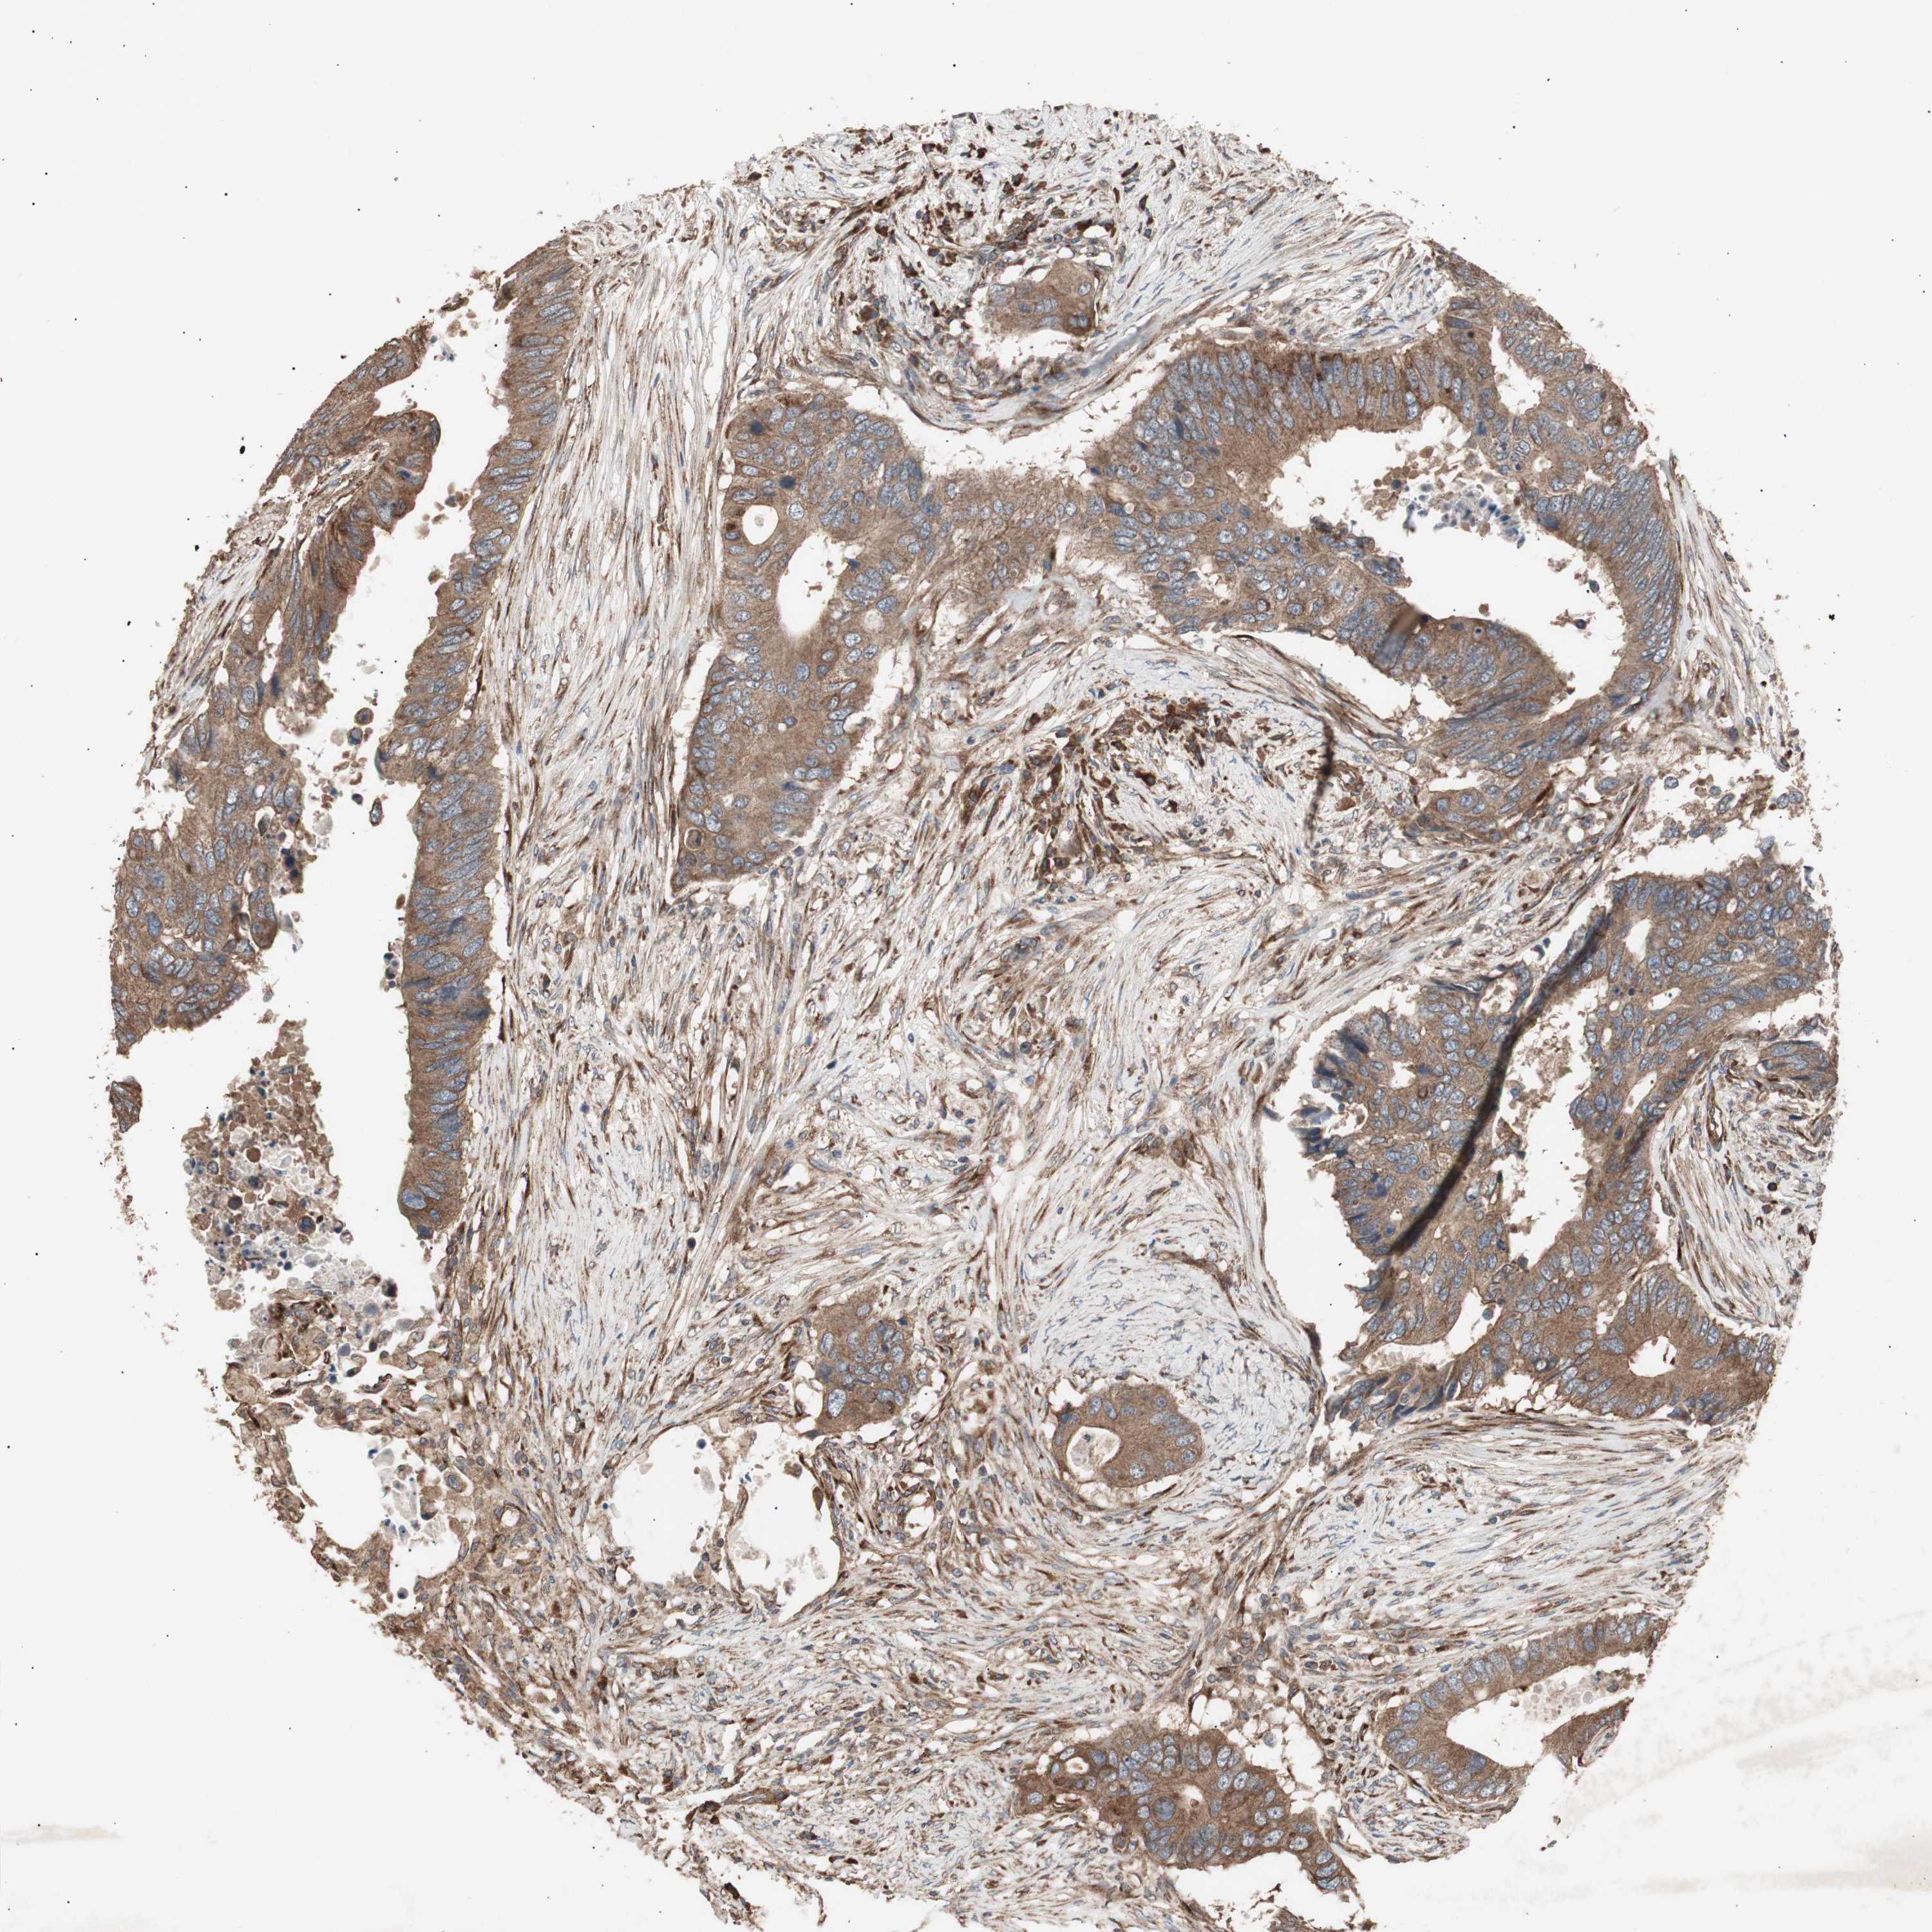

CANCER COLORECTAL CANCER Show tissue menu

Colorectal cancer

Human cancer

Colon adenocarcinoma